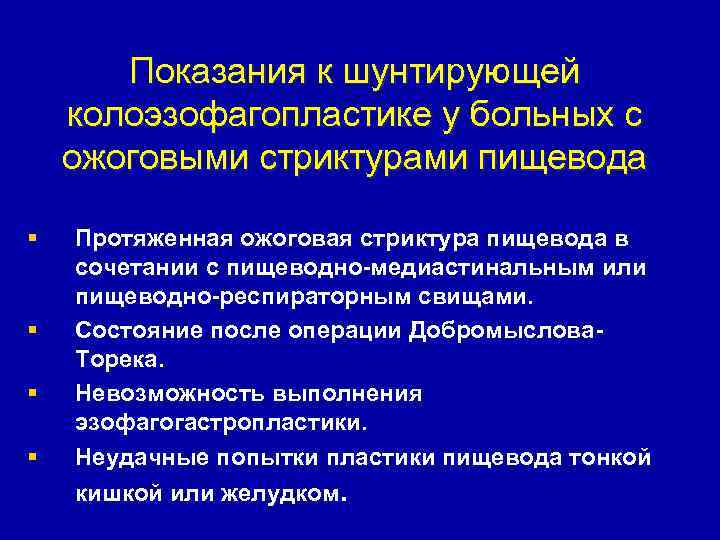

Показания к шунтирующей колоэзофагопластике у больных с ожоговыми стриктурами пищевода § § Протяженная ожоговая стриктура пищевода в сочетании с пищеводно-медиастинальным или пищеводно-респираторным свищами. Состояние после операции Добромыслова. Торека. Невозможность выполнения эзофагогастропластики. Неудачные попытки пластики пищевода тонкой кишкой или желудком.